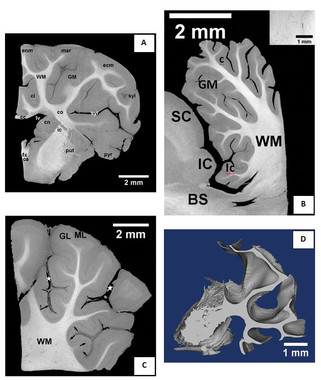

En el CENIEH se ha llevado a cabo el escaneado y el análisis de este tejido cerebral de un mamífero, en concreto de un cordero. El alto contraste logrado entre los dos compartimentos del encéfalo, así como la alta resolución obtenida (8 micras), superior a la lograda por microresonancia magnética (10 veces menor), permite la segmentación y posterior reconstrucción en 3D de la sustancia blanca.

Cortes de tejido cerebral de cordero en los que se diferencian la sustancia blanca de la gris. (Foto: Belén Notario)

Con esta técnica, que usa el dicromato de potasio como agente de contraste, se pueden visualizar también otros elementos neuronales y no neuronales del tejido nervioso, como la piamadre (meninge interna que protege el sistema nervioso central) y los vasos sanguíneos, así como otras partes anatómicas.